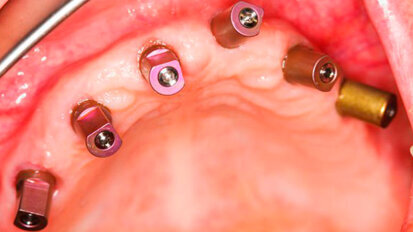

Impianti trans-sinusali per la riabilitazione del mascellare atrofico: serie di 32 casi in pazienti totalmente edentuli

La possibilità di riabilitare una arcata totalmente edentula mediante l’inserimento di impianti osteointegrati e il posizionamento di una ...